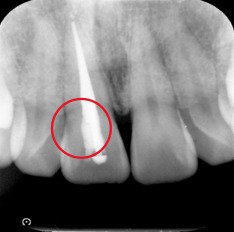

同部位は過去に神経の治療を行っていました。

患者様は歯ぎしり食いしばりがあり、マウスピースを睡眠時に使用して予防していました。しかし神経の治療をしてから長期間経過していたこともあり、歯質にヒビがあることを確認しました。

このままではいずれ歯質が欠けてしまい、最悪の場合、欠けた場所によっては抜歯となる可能性があります。そのため歯質を覆う被せ物の治療を患者様に提案し、治療を行いました。